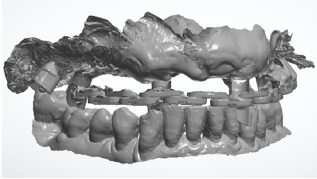

At the end of the surgical session, the position of the implants was defined by the use of specific scan bodies connected to each other through the use of the universal scan template. Then, the post-surgical digital scan was carried out, including the entire maxilla, the skeletal scan bodies, the implant scan bodies and the universal scan template (Figure 14).

Figure 14: Post-surgical digital scan including the entire maxilla, the skeletal scan bodies, the implant scan bodies and the universal scan template.